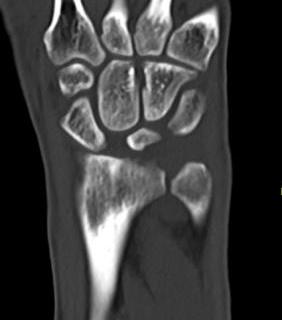

AP X-ray

Disruption of Gilula's 3 smooth carpal arcs / triangular lunate

Normal versus disruputed Gilula's carpal arcs

Piece of pie / triangular appearance of lunate

CT

Trans-scaphoid perilunate dislocation

Perilunate dislocation